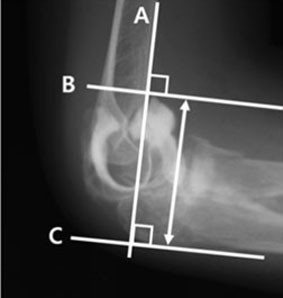

Á¤Çü¿Ü°ú °ü·Ã ±¹Á¦ÇмúÁöÀÎ ¡®Journal of Orthopaedics¡¯¿¡ °ÔÀçµÈ ¡®Proper elbow arthroscopy portal placement in pediatric and adolescent patients¡¯ ³í¹®Àº ÃÖ±Ù ¸¹ÀÌ »ç¿ëµÇ°í ÀÖ´Â ÁÖ°üÀý ³»½Ã°æ Ä¡·á¿¡ ÀÖ¾î¼ ¼Ò¾Æ ¹× û¼Ò³â±â ȯÀÚ Ä¡·á ½Ã ÀûÀýÇÑ »ðÀÔ±¸ À§Ä¡¿¡ ´ëÇØ º¸°íÇÑ ³í¹®ÀÌ´Ù.

¼Ò¾Æ ¹× û¼Ò³â±âÀÇ ÁÖ°üÀýÀº °ñÇü¼ºÀÌ ¿Ï·áµÇÁö ¾Ê¾Æ ±âÁ¸ÀÇ »ðÀÔ±¸ À§Ä¡·Î »ç¿ëÇÏ´ø ÁöÇ¥¿¡´Â ÇѰ谡 ÀÖ´Ù. ÀÌ¿¡ µû¶ó À̹ø À¯À缺 ±³¼öÀÇ ÆÈ²ÞÄ¡ ³»½Ã°æ Ä¡·á¿¡ ´ëÇÑ ³í¹®Àº ´Ù¾çÇÑ °ñ¼º ÁöÇ¥¸¦ Á¦½ÃÇÑ ¿¬±¸¶ó´Â Á¡¿¡¼ ±× ÀÇÀǰ¡ ÀÖ´Ù°í ÇÒ ¼ö ÀÖ´Ù.

| | | ¡è¡è ¡ã°üÀý Á¶¿µ¼úÀ» ÀÌ¿ëÇÑ °üÀý³¶ÀÇ À§Ä¡ ÃøÁ¤ <»çÁøÁ¦°ø=¾Æ»êÃæ¹«º´¿ø> | ¨Ï ¿Â¾ç½Å¹® | | À¯À缺 ±³¼ö´Â ¡°À̹ø ¿¬±¸¸¦ ÅëÇØ ´Ù¾çÇÑ °ñ¼º ÁöÇ¥¸¦ Á¦½ÃÇÔ°ú µ¿½Ã¿¡ ¼Ò¾Æ ¹× û¼Ò³â ȯÀڵ鿡°Ô º¸´Ù ´õ ÀûÀýÇÑ Ä¡·á¸¦ Á¦°øÇÒ ¼ö ÀÖÀ» °ÍÀ¸·Î ±â´ëµÈ´Ù´Â Á¡¿¡¼ À¯ÀǹÌÇÑ ¿¬±¸¿´´Ù°í »ý°¢ÇÑ´Ù. ¾ÕÀ¸·Îµµ ȯÀڵ鿡°Ô ÃÖ¼±ÀÇ Áø·á¸¦ Á¦°øÇÒ ¼ö ÀÖµµ·Ï ³ë·ÂÇϰڴÙ.¡±°í ¸»Çß´Ù.